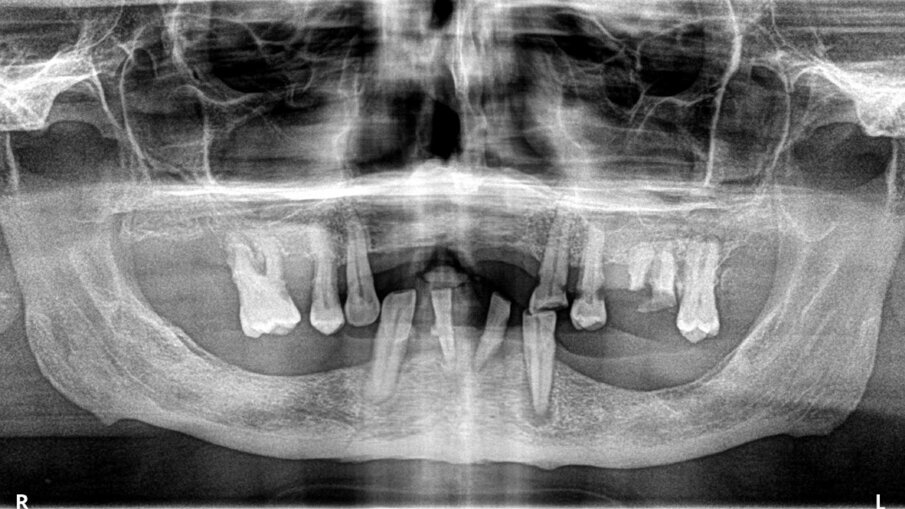

Il paziente si presentò alla nostra osservazione lamentando una diminuzione della capacità masticatoria. All’osservazione clinica e radiografica (Figg. 1, 2) si evidenziava la mancanza di numerosi elementi dentari e di una diffusa malattia parodontale, il tutto complicato dalla presenza di carie destruenti su tutti gli elementi dentari con migrazione degli stessi. Lo spostamento dei denti aveva portato a perdita della dimensione verticale e di tutti i punti di riferimento per la ricostruzione della dentatura.

Al paziente fu spiegato che la strategia migliore consisteva nell’estrazione di tutti gli elementi dentari e l’inserimento di sei impianti in ogni arcata dentaria e successivamente il ripristino delle arcate con due protesi tipo Toronto. Si decise di non estrarre subito i quattro canini perché sarebbero serviti per stabilizzare le mascherine chirurgiche durante la chirurgia. Lo studio del caso e la sua realizzazione fu fatta con metodo analogico. Due modelli in gesso furono montati alla giusta dimensione verticale e fu realizzato il montaggio dei denti per visualizzare il risultato finale (Fig. 3). Dal montaggio dei denti furono realizzate le mascherine chirurgiche che sarebbero state utilizzate per gli esami radiografici tridimensionali e avrebbero guidato il posizionamento degli impianti durante la chirurgia. All’esame radiografico tridimensionale (Figg. 4-7) si notava la presenza di una quantità esigua di osso coronalmente ai seni mascellari e al nervo alveolare inferiore. Si decise di inserire impianti extracorti 4,5 mm di lunghezza in queste zone, per evitare sia impianti inclinati sia cantilever molto estesi. Lo studio della scala dei grigi, o scala Hounsfield, mostrava una densità ossea tale da consentire il carico immediato anche in queste zone. Ovviamente sarebbe stata necessaria la conferma intra-operatoria valutando clinicamente la compattezza dell’osso tramite la fresatura.